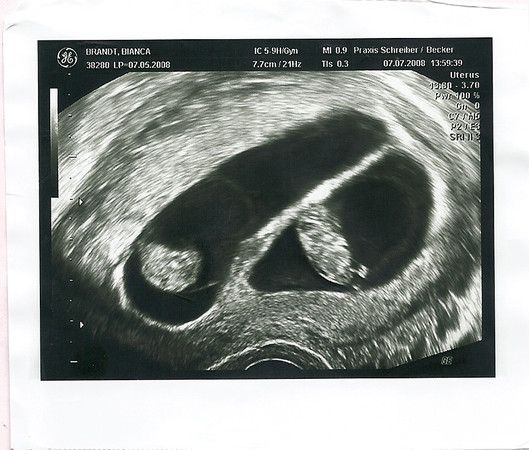

Meine Mäuse sind mit wöchiger verfrühung spontan zur Welt gekommen. Allerdings nach Einleitung.

Am 24.01.2012 war es dann endlich soweit.

Mia-Sophy kam um 10:55 uhr mit 43 cm und 1830gramm zur Welt. Ihre Schwester Lina-Josefine folgte ihr 6 min später mit 45 cm und 2190 gramm